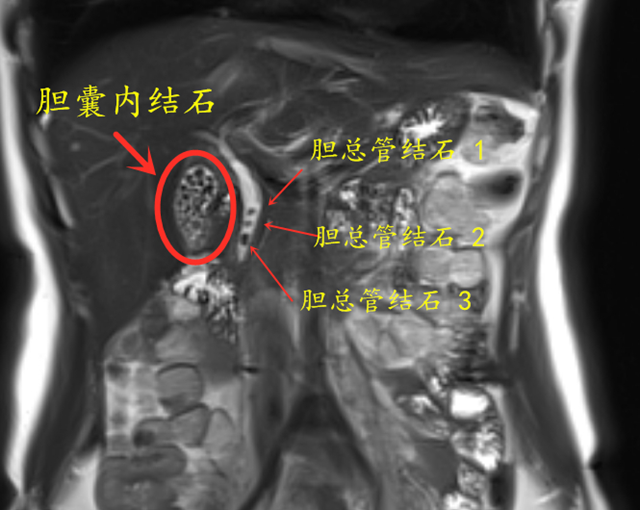

检查发现,充满胆囊的结石已然不是最严重的问题了,因为从胆囊里掉出来的结石,已经排着队卡在胆总管上了,胆汁只能从石头缝中排入肠道。

经过科室讨论,肝胆胰外科团队决定为小李施行腹腔镜胆囊切除术+胆总管切开取石术。

术中,肝胆胰外科主任陆昌友教授带领手术团队切除了充满石头的胆囊,然后使用“双镜联合”,在腹腔镜的引导下,向胆总管置入胆道镜,最终取出“误入歧途”的结石。

相较于大个头的胆囊结石,小个头的结石更容易从胆囊掉出来,堵塞胆总管,引起更加严重的问题,如梗阻性黄疸(对,就是像小黄人那样的)、急性梗阻性胆管炎及急性胰腺炎(这两个都是要命的)。